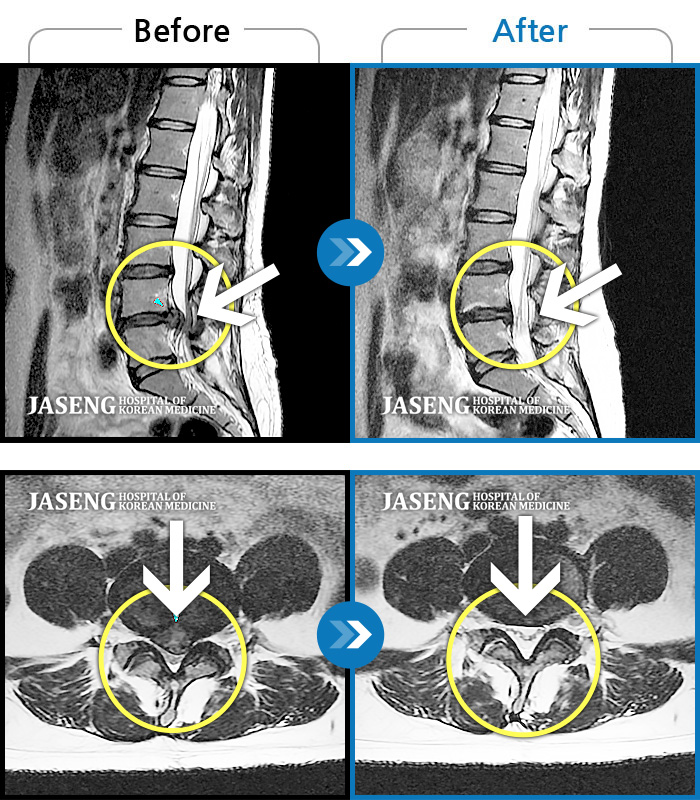

허리디스크

보라매 · 왕오호 원장

좌측 허리 통증과 좌측 다리 저림

촬영시기

2017.08.26 ~ 2018.08.21

2018.12.28